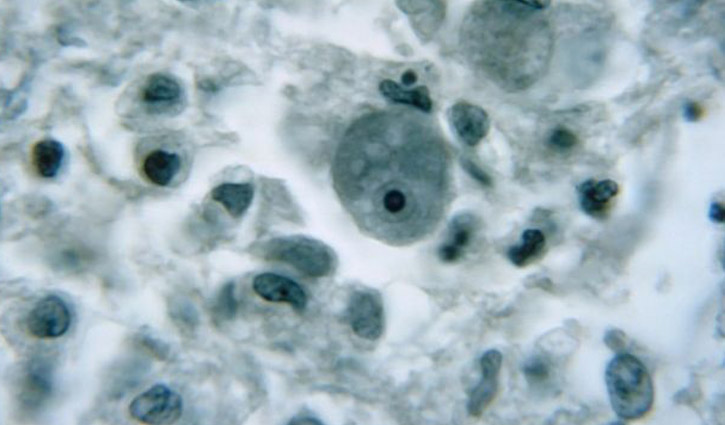

ফ্লোরিডা স্বাস্থ্য দফতরের বরাত দিয়ে একজনের মস্তিষ্কে ‘নাইজেলেরিয়া ফাউলেরি’র সংক্রমণের খবর নিশ্চিত করেছে ব্রিটিশ সংবাদমাধ্যম বিবিসি। এককোষী এই অ্যামিবা মস্তিষ্কে সংক্রমণের প্রধান কারণ এবং প্রাণঘাতী। সাধারণত উষ্ণ স্বাদু পানিতে পাওয়া যায় এই মস্তিষ্কখেকো অ্যামিবা, নাকের মাধ্যমে শরীরে ঢুকে মস্তিষ্কের ক্ষতি করে। কোথায় থেকে এই সংক্রমণ প্রথম শুরু হলো কিংবা রোগীর অবস্থা সম্পর্কে কিছু জানায়নি ফ্লোরিডার স্বাস্থ্য দফতর। আশার কথা হলো, এই অ্যামিবা ব্যক্তি থেকে ব্যক্তিতে সংক্রমিত হয় না। এই ধরনের সংক্রমণ সাধারণত যুক্তরাষ্ট্রের দক্ষিণাঞ্চলীয় রাজ্যে হয়ে থাকে। ফ্লোরিডায় তা বিরল, যেখানে ১৯৬২ সাল থেকে কেবল ৩৭ জন এই রোগে আক্রান্ত হন। নতুন রোগী খুঁজে পাওয়ায় সম্ভাব্য মারাত্মক পরিস্থিতি এড়াতে ৩ জুলাই থেকে হিলসবোরোর বাসিন্দাদের সতর্ক করে কর্তৃপক্ষ।